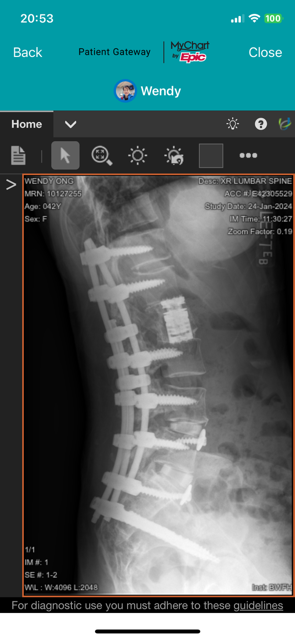

(2024 Update): After my December 26, 2023 surgery to extend my fusion from L4 to S1, and redo my T11 to L4 instrumentation, my lumbar region now looks like this.